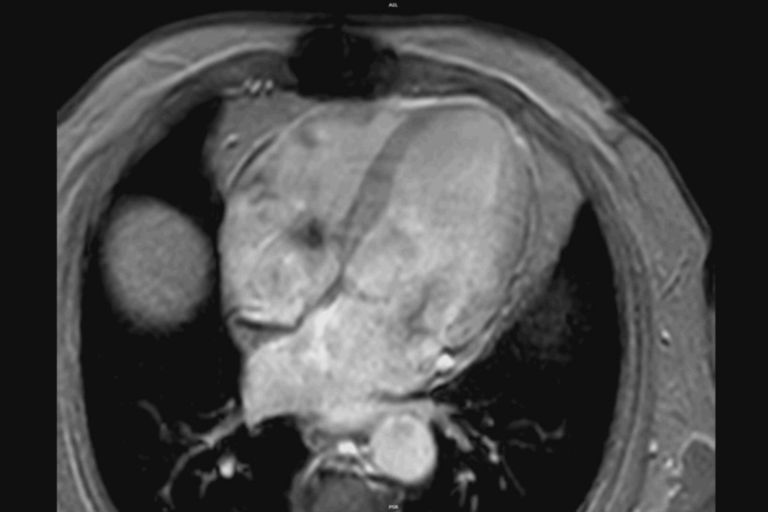

Cardiac MR of non-ischemic cardiomyopathy showing delayed enhancement and severe mitral regurgitation.

Cardiomyopathy. Cardiac MR images of a patient with non-ischemic cardiomyopathy showing delayed enhancement and severe mitral regurgitation.